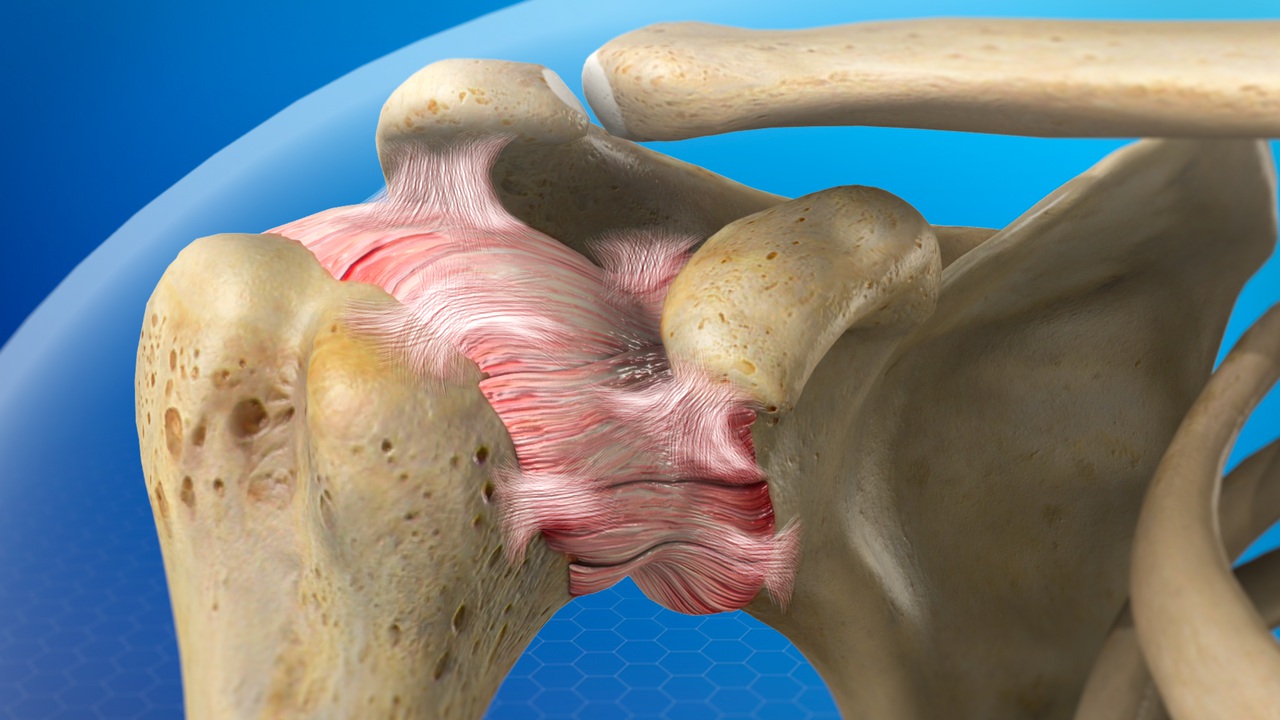

Shoulder Arthroscopy

Similar to the knee, arthroscopy in the shoulder was first used for diagnostic purposes before being expanded to include therapeutic purposes. A variety of disorders affecting the shoulder joint can be evaluated by orthopedic surgeons using the minimally invasive shoulder arthroscopy procedure.